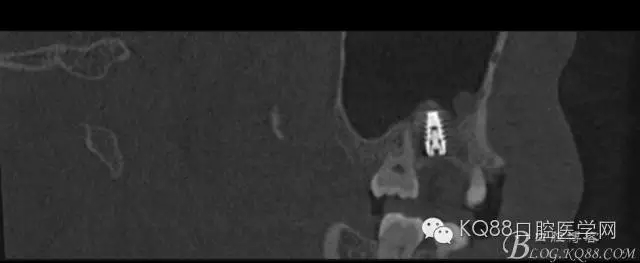

植入后,CBCT

另外一個(gè)切面。竇底粘膜完整連續(xù)??梢钥吹缴舷乱Ш系奈恢藐P(guān)系。